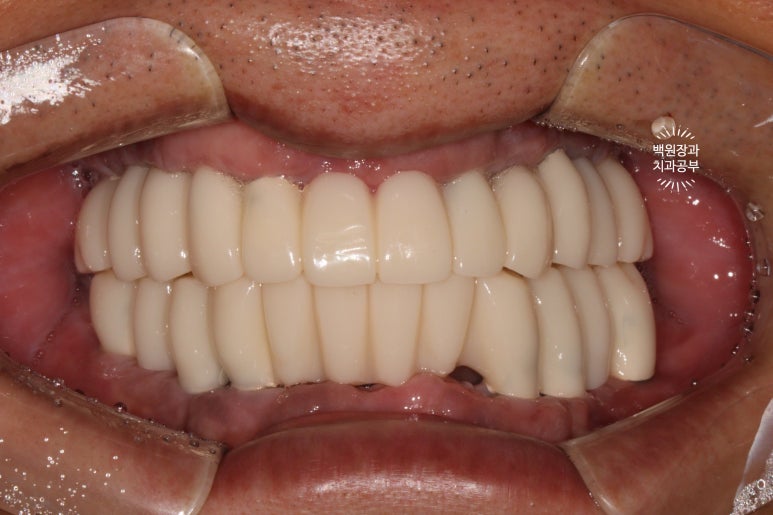

시간이 지나.. 최종 보철물을 만들어드리는 시간입니다.

약 한달간의 씹는 연습을 마치게 되면, 이제 본격적으로 최종 보철물을 제작해드리게 됩니다.

지르코니아 재질로 만들어진 크라운은 심미적으로도 유리하며, 그 단단함은 성인 남성이 넉넉히 사용하여도 깨지지 않을 정도에요.

치아 색이 약간 노랗다 생각하실수도 있으나, 피부색에 맞추어 제작되므로 너무 걱정하진 마세요!

이렇게 보면 측면 모습도 상당히 괜찮고....

잘 보시면 치아와 치아 사이에 틈이 있는 것을 보실 수 있으실텐데요, 이 경계는 앞니 보철물/어금니 보철물의 경계로 추후에 보철물의 수리가 용이하기 하기 위함입니다. 더불어 치실을 쓸 수 있게 하는 공간으로 반드시 필요한 포인트!

이젠 치아가 생겨서, 식사를 하실 수 있게 되었습니다.

잘 제작된 보철물은 앞니로 면도 끊어먹을 수 있어서 환자분들께 크나큰 만족감을 줍니다.